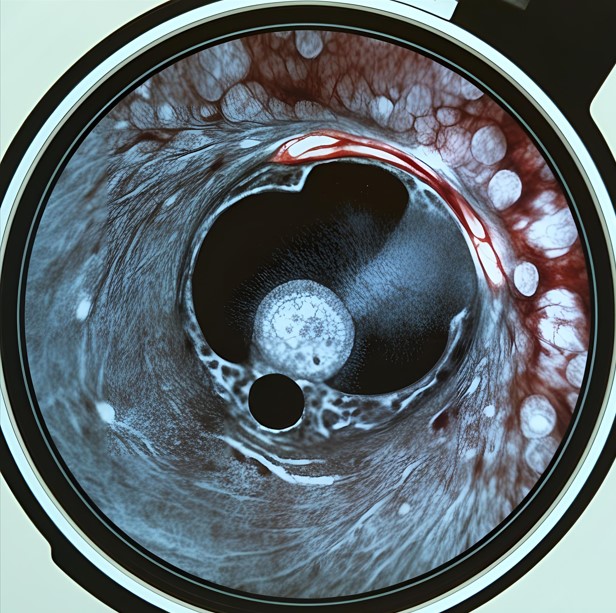

1) 내시경 점막 절제술(ESD, EMR)

위암이 점막층에 국한된 초기 단계라면, 내시경을 이용해 암 조직을 제거할 수 있습니다. 이는 비교적 간단한 시술로 회복도 빠릅니다.